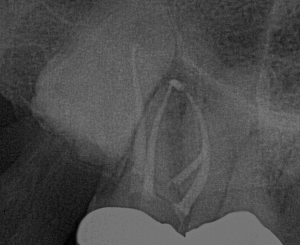

The patient presented with a referral for root canal treatment of tooth #3. Pulp vitality testing indicated that #3 was vital, while #2 was necrotic. CBCT revealed that a large area of low density was associated with #2 and was encroaching on #3, therefore giving the appearance that #3 may also need root canal treatment. The patient and I agreed that incision and drainage, along with root canal treatment of #2, was the best first-line treatment.

Tooth #2 had 4 calcified, necrotic canals. The

EndoPilot and

Procodile Q™ files were instrumental in completing this case safely and efficiently in a single visit. The Ultrasonic attachment on the EndoPilot was critical for accessing the MB2, especially in this area of the mouth where access can be a challenge!